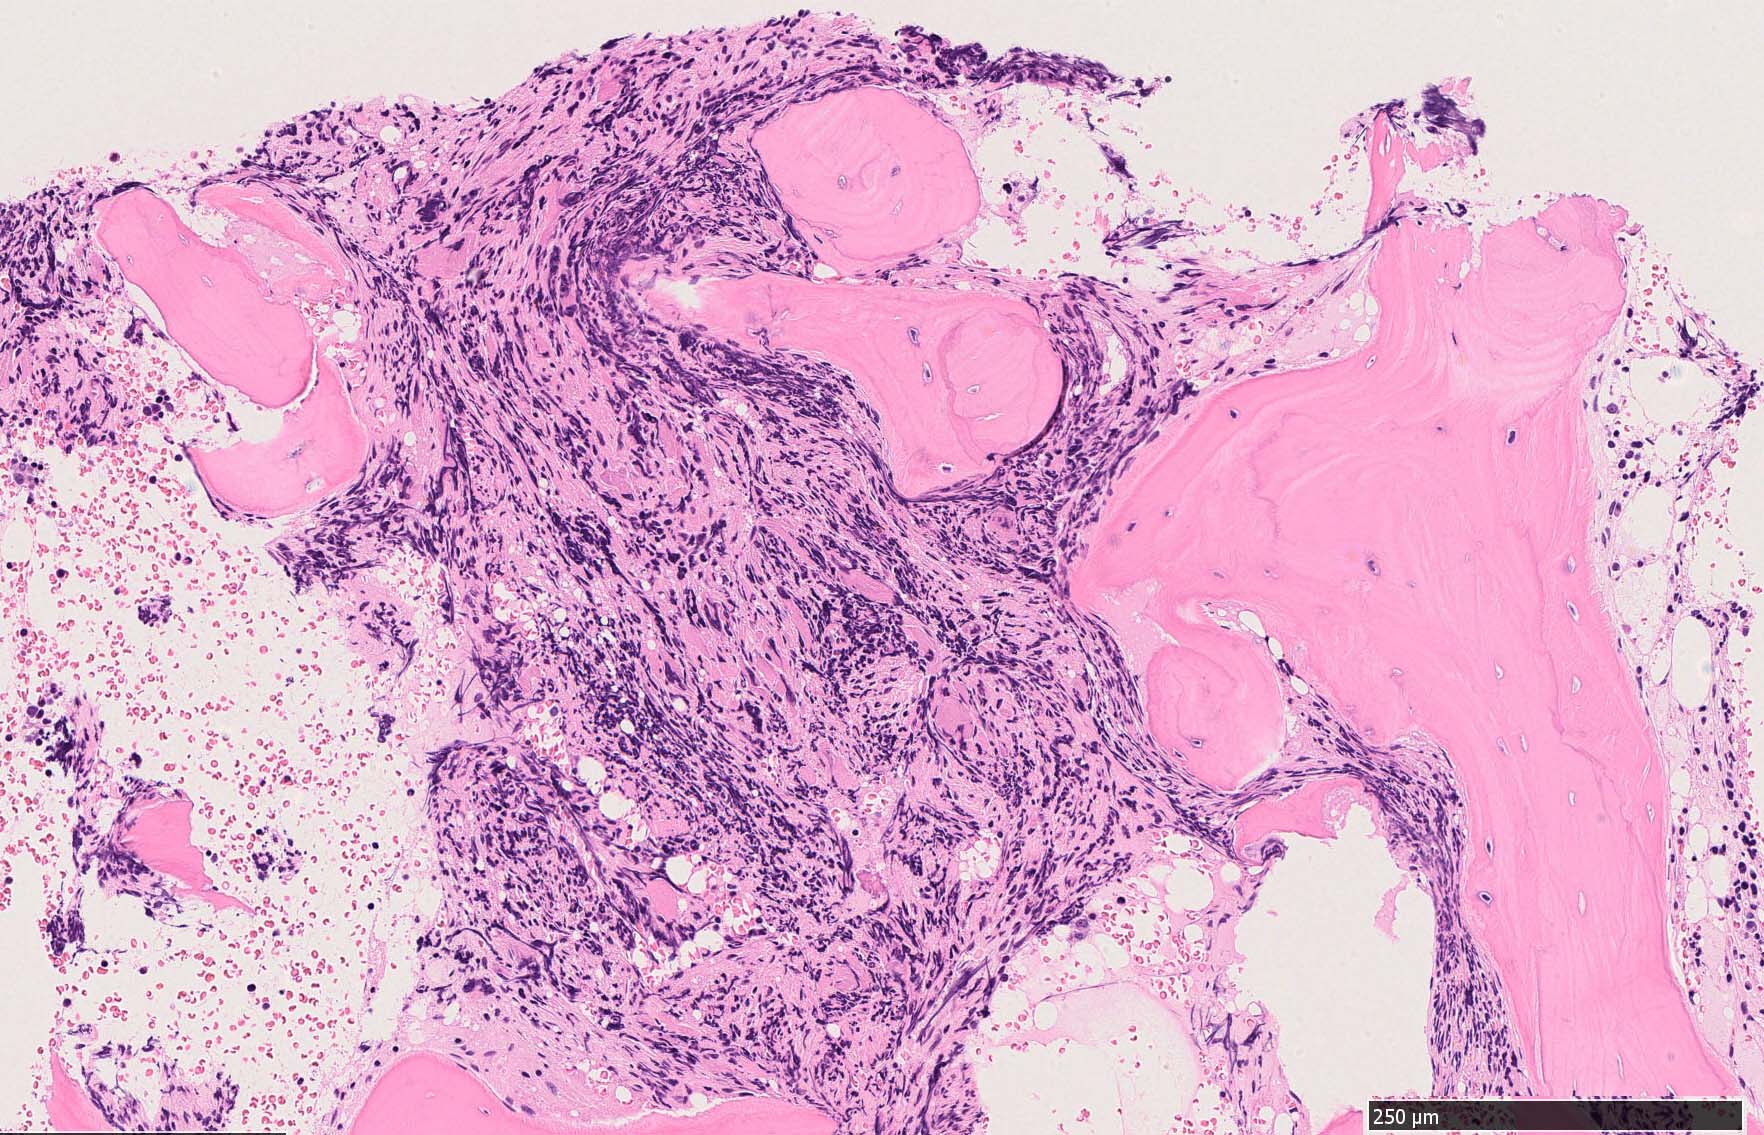

骨髄組織所見 bone marrow biopsy total 6mm in length

Case02; Meylofibrosis, overt fibrosis

黒染する弾性線維の増生のほか, 赤く染まる膠原線維の増生が確認される. MF-2 fibrosis. 鍍銀染色の核染色をすると膠原線維の赤染がわからなくなるので行わない.